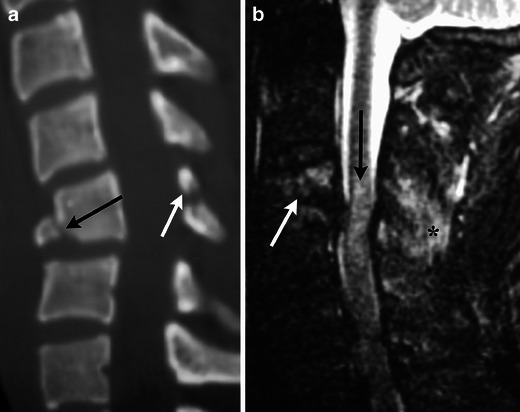

Fig. 13.

Clay shoveller’s fracture. (a) Sagittal MDCT image demonstrates avulsion fractures of C7 and T1 (white arrow). (b) Sagittal STIR image demonstrates marrow oedema within the spinous process (black asterisk) as well as injury to the intraspinous and supraspinous ligaments (white arrow)